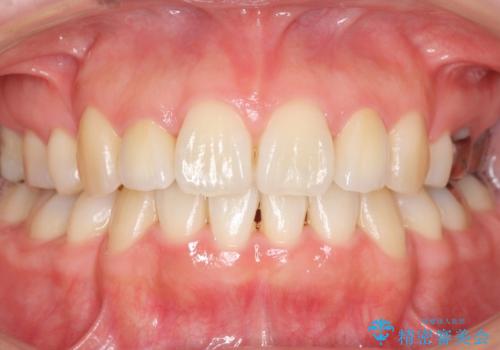

矯正治療後、矮小歯をセラミッククラウンにより理想的な歯の大きさに仕上げました。

自然な仕上がりにご満足頂けました。

「自分でもどこを治したのかわからないくらい自然!」と喜んで下さいました。

クラウンの種類:オールセラミッククラウン スペシャル